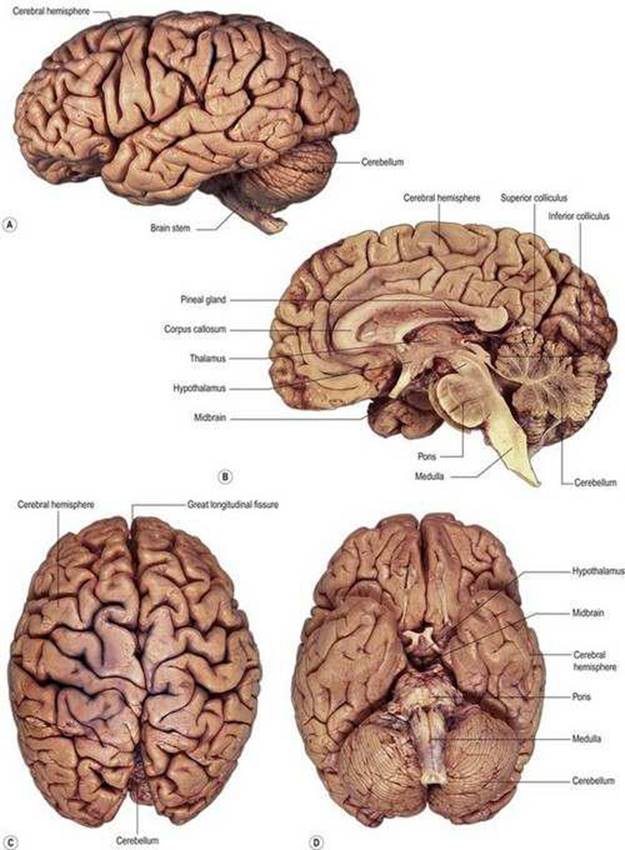

شکل ۱.۱۱ عکسهای مغز. الف) جنبه جانبی؛ (ب) بخش ساژیتال میانه. (ج) جنبه پشتی؛ (د) جنبه شکمی.

شکل ۱.۱۱ عکسهای مغز. الف) جنبه جانبی؛ (ب) بخش ساژیتال میانه. (ج) جنبه پشتی؛ (د) جنبه شکمی.

شکل ۱.۱۲ تقسیمات فرعی اصلی و برخی از نشانههای مهم در مغز بالغ. (الف) بخش ساژیتال میانه؛ (ب) جنبه شکمی. اعصاب اعصاب جمجمه ای با رنگ زرد نشان داده شده اند.

فرآیند پرونسفالیزاسیون به این معنی بود که سایر مراکز به تدریج تابع نیمکرههای مغزی شدند. برای مثال، آنهایی که برای بینایی و شنوایی هستند، رشد نسبتا کمیداشتند و عملکردهای بازتابی و خودکار را در مغز انسان انجام میدهند. با این حال، هنوز هم ممکن است به عنوان چهار تورم کوچک در سطح پشتی مغز میانی شناسایی شوند: corpora quadrigemina یا کولیکولهای فوقانی و تحتانی (شکلهای ۱.۱۰ – ۱.۱۲). مرکز حرکتی نزدیک انتهای دمیمغز به مخچه توسعه یافته است (شکلهای ۱.۱۰ – ۱.۱۲) که نقش اصلی را در حفظ تعادل و هماهنگی حرکت حفظ میکند.

آناتومی مغز

ویژگیها و نشانههای اصلی

مغز تحت سلطه نیمکرههای مغزی است (شکلهای ۱.۱۱، ۱.۱۲). اینها یک گوشته بیرونی بسیار پیچیده از ماده خاکستری و یک هسته داخلی از ماده سفید دارند. برخی از پیچشهای سطحی عملکردهای حسی یا حرکتی خاصی دارند که در زیر توضیح داده شده است. دو نیمکره مغزی به طور ناقص توسط یک شکاف طولی بزرگ از هم جدا شده اند. شکاف به طور معمول توسط فلکس سربری اشغال میشود و در اعماق آن جسم پینه ای قرار دارد که حاوی الیاف همسو است که مناطق متناظر دو نیمکره را متحد میکند.

هنگامیکه مغز به صورت شکمیمشاهده میشود، ساقه مغز به وضوح دیده میشود، اگرچه روابط مغز میانی به بهترین وجه در بخش ساژیتال نشان داده میشود. ساقه مغز منشا اعصاب جمجمه III-XII است. پشتی (خلفی) به ساقه مغز مخچه قرار دارد. مخچه تنتوریوم معمولاً بین مخچه و قسمت خلفی (لوبهای پس سری) نیمکرههای مغز قرار دارد.

ساقه مغز

هنگامیکه مغز به صورت خارجی مشاهده میشود، نیمکرههای بزرگ مغز بسیاری از ساختارهای دیگر را مبهم میکند، اما یک بخش ساژیتال وسط (شکل ۱.11B، ۱.12A) بیشتر ویژگیهای اصلی مغز اصلی را نشان میدهد. ساقه مغز را میتوان به وضوح در هر دو بخش ساژیتال وسط و نمای شکمی(شکل ۱.۱۱، ۱.۱۲) مغز مشاهده کرد. ساقه مغز از بصل النخاع، پونز و مغز میانی تشکیل شده است.

مغز میانی نسبتاً کوچکی در منقاری بر روی پونز قرار دارد. در سطح پشتی آن میتوان برجستگیهای گرد کولیکولهای فوقانی و تحتانی را مشاهده کرد که در زیر آنها قنات مغزی قرار دارد (شکلهای ۱.۱۰ – ۱.۱۲).

دیانسفالون و نیمکرههای مغزی

منقاری به ساقه مغز، جلوی مغز قرار دارد که از دیانسفالون و نیمکرههای مغزی تشکیل شده است. دیانسفالون و نیمکره مغز در هر طرف مغز تا حد زیادی از نظر فیزیکی از همتایان خود در طرف دیگر جدا هستند، اگرچه اتصالات متقابل مهمیوجود دارد، همانطور که در زیر توضیح داده شده است. دو طرف دیانسفالون توسط لومن بطن سوم که دیوارههای جانبی آن را تشکیل میدهند از هم جدا میشوند.

دیانسفالون از چهار بخش اصلی در جهت پشتی شکمیتشکیل شده است: اپی تالاموس، تالاموس، ساب تالاموس و هیپوتالاموس. اپیتالاموس کوچک است و قابل توجه ترین جزء آن غده صنوبری است که در خط وسط قرار دارد و بلافاصله به سمت کولیکولهای فوقانی مغز میانی قرار دارد (شکل ۱.12A). تالاموس بزرگترین قسمت دیانسفالون است و بیشتر دیواره جانبی بطن سوم را تشکیل میدهد. تالاموس نقش مهمیدر عملکردهای حسی، حرکتی و شناختی دارد و ارتباطات متقابل گسترده ای با قشر مغز دارد. ساب تالاموس ناحیه کوچکی است که در عمق دیواره بطن قرار دارد. حاوی هسته ساب تالاموس استکه از نظر عملکردی نزدیک به عقدههای قاعده ای مرتبط است (فصل ۱۴). هیپوتالاموس قسمت پایینی دیوارهها و کف بطن سوم را تشکیل میدهد. این یک منطقه پیچیده و بسیار مهم است زیرا در سیستم عصبی خودمختار (فصل ۴)، سیستم لیمبیک و سیستم عصبی غدد درون ریز (فصل ۱۶) دخالت دارد. از قسمت شکمیهیپوتالاموس در خط میانی، ساقه زیرین یا هیپوفیز بیرون میآید که غده هیپوفیز به آن متصل است (شکل ۱.۱۲).

نیمکره مغز تا حد زیادی بزرگترین بخش مغز است. مانند مخچه، از یک لایه بیرونی یا قشر از ماده خاکستری و یک توده داخلی از ماده سفید تشکیل شده است (شکل ۱.۲۰، ۱.۲۱). علاوه بر این، تا حدی در داخل ماده سفید زیر قشری چندین توده بزرگ از اجسام سلولی قرار دارند که در مجموع به آنها عقدههای پایه میگویند (شکلهای ۱.۵، ۱.۲۰، ۱.۲۱). دو نیمکره مغزی توسط یک شکاف خط میانی عمیق، شکاف طولی بزرگ (شکل ۱.۲۰) از هم جدا میشوند که فالکس سربری (falx cerebri) را در خود جای میدهد. در اعماق شکاف جسم پینه ای قرار دارد (شکل ۱.12A، ۱.۲۰)، ورقه بزرگی از رشتههای عصبی متقاطع (فیبرهای کمسیورال) که نواحی متناظر دو قشر مغز را به هم متصل میکند.